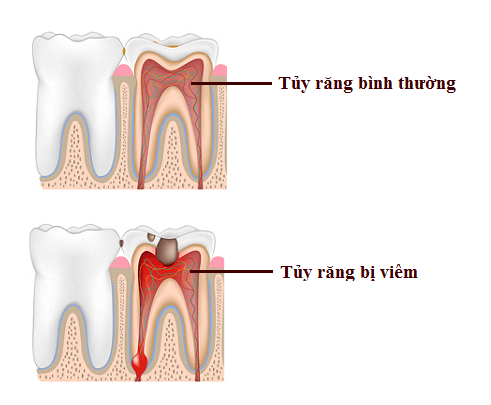

Viêm tủy, nguy cơ hỏng cả răng gốc

Nguyên nhân dẫn đến viêm tủy sau khi bọc sứ được xác định là do kỹ thuật bọc sứ của bác sĩ không đảm bảo quy chuẩn Y khoa, có nghĩa là:

- Trường hợp bác sĩ không điều trị tuỷ răng, hoặc không điều trị dứt điểm vấn đề răng thật bị sâu, bị vôi răng, viêm nướu, viêm nha chu.

- Bác sĩ thiếu kinh nghiệm chuyên môn thực hiện có thể mài quá nhiều mô răng khiến cho cấu trúc răng bị can thiệp sâu. Hành động này có thể phạm vào sừng tuỷ hoặc sát tuỷ, vị khuẩn xâm nhập vào tuỷ gây viêm tuỷ.

- Mài cùi răng không đúng kỹ thuật: Sử dụng hệ thống tay khoan không đạt tiêu chuẩn, khả năng tưới nước kém, hệ thống mũi khoan quá cùn và rung lắc nhiều dẫn tới sinh nhiệt tại răng mài do ma sát giữa múi khoan và mô răng, làm cho tủy bị tổn thương.

- Do không làm răng tạm đúng quy cách hoặc không làm răng tạm: Nhiều phòng khám nha khoa cắt giảm khâu làm răng tạm hoặc chỉ làm răng tạm sơ sài bằng Composite, dẫn tới hậu quả viêm tủy răng sau khi gắn răng sứ tăng lên. Do Sau khi mài, cùi răng còn lại đã bị mất men, chỉ còn lớp ngà và tủy răng. Nếu răng sau mài không được bảo vệ bằng răng tạm hoặc răng tạm không tốt, không đủ kín vi khuẩn từ môi trường miệng sẽ xâm nhập vào tủy gây viêm tủy răng.

Nguyên nhân chính khiến viêm tuỷ răng sau khi bọc sứ do chất lượng dịch vụ, sản phẩm được sử dụng và tay nghề của bác sĩ.